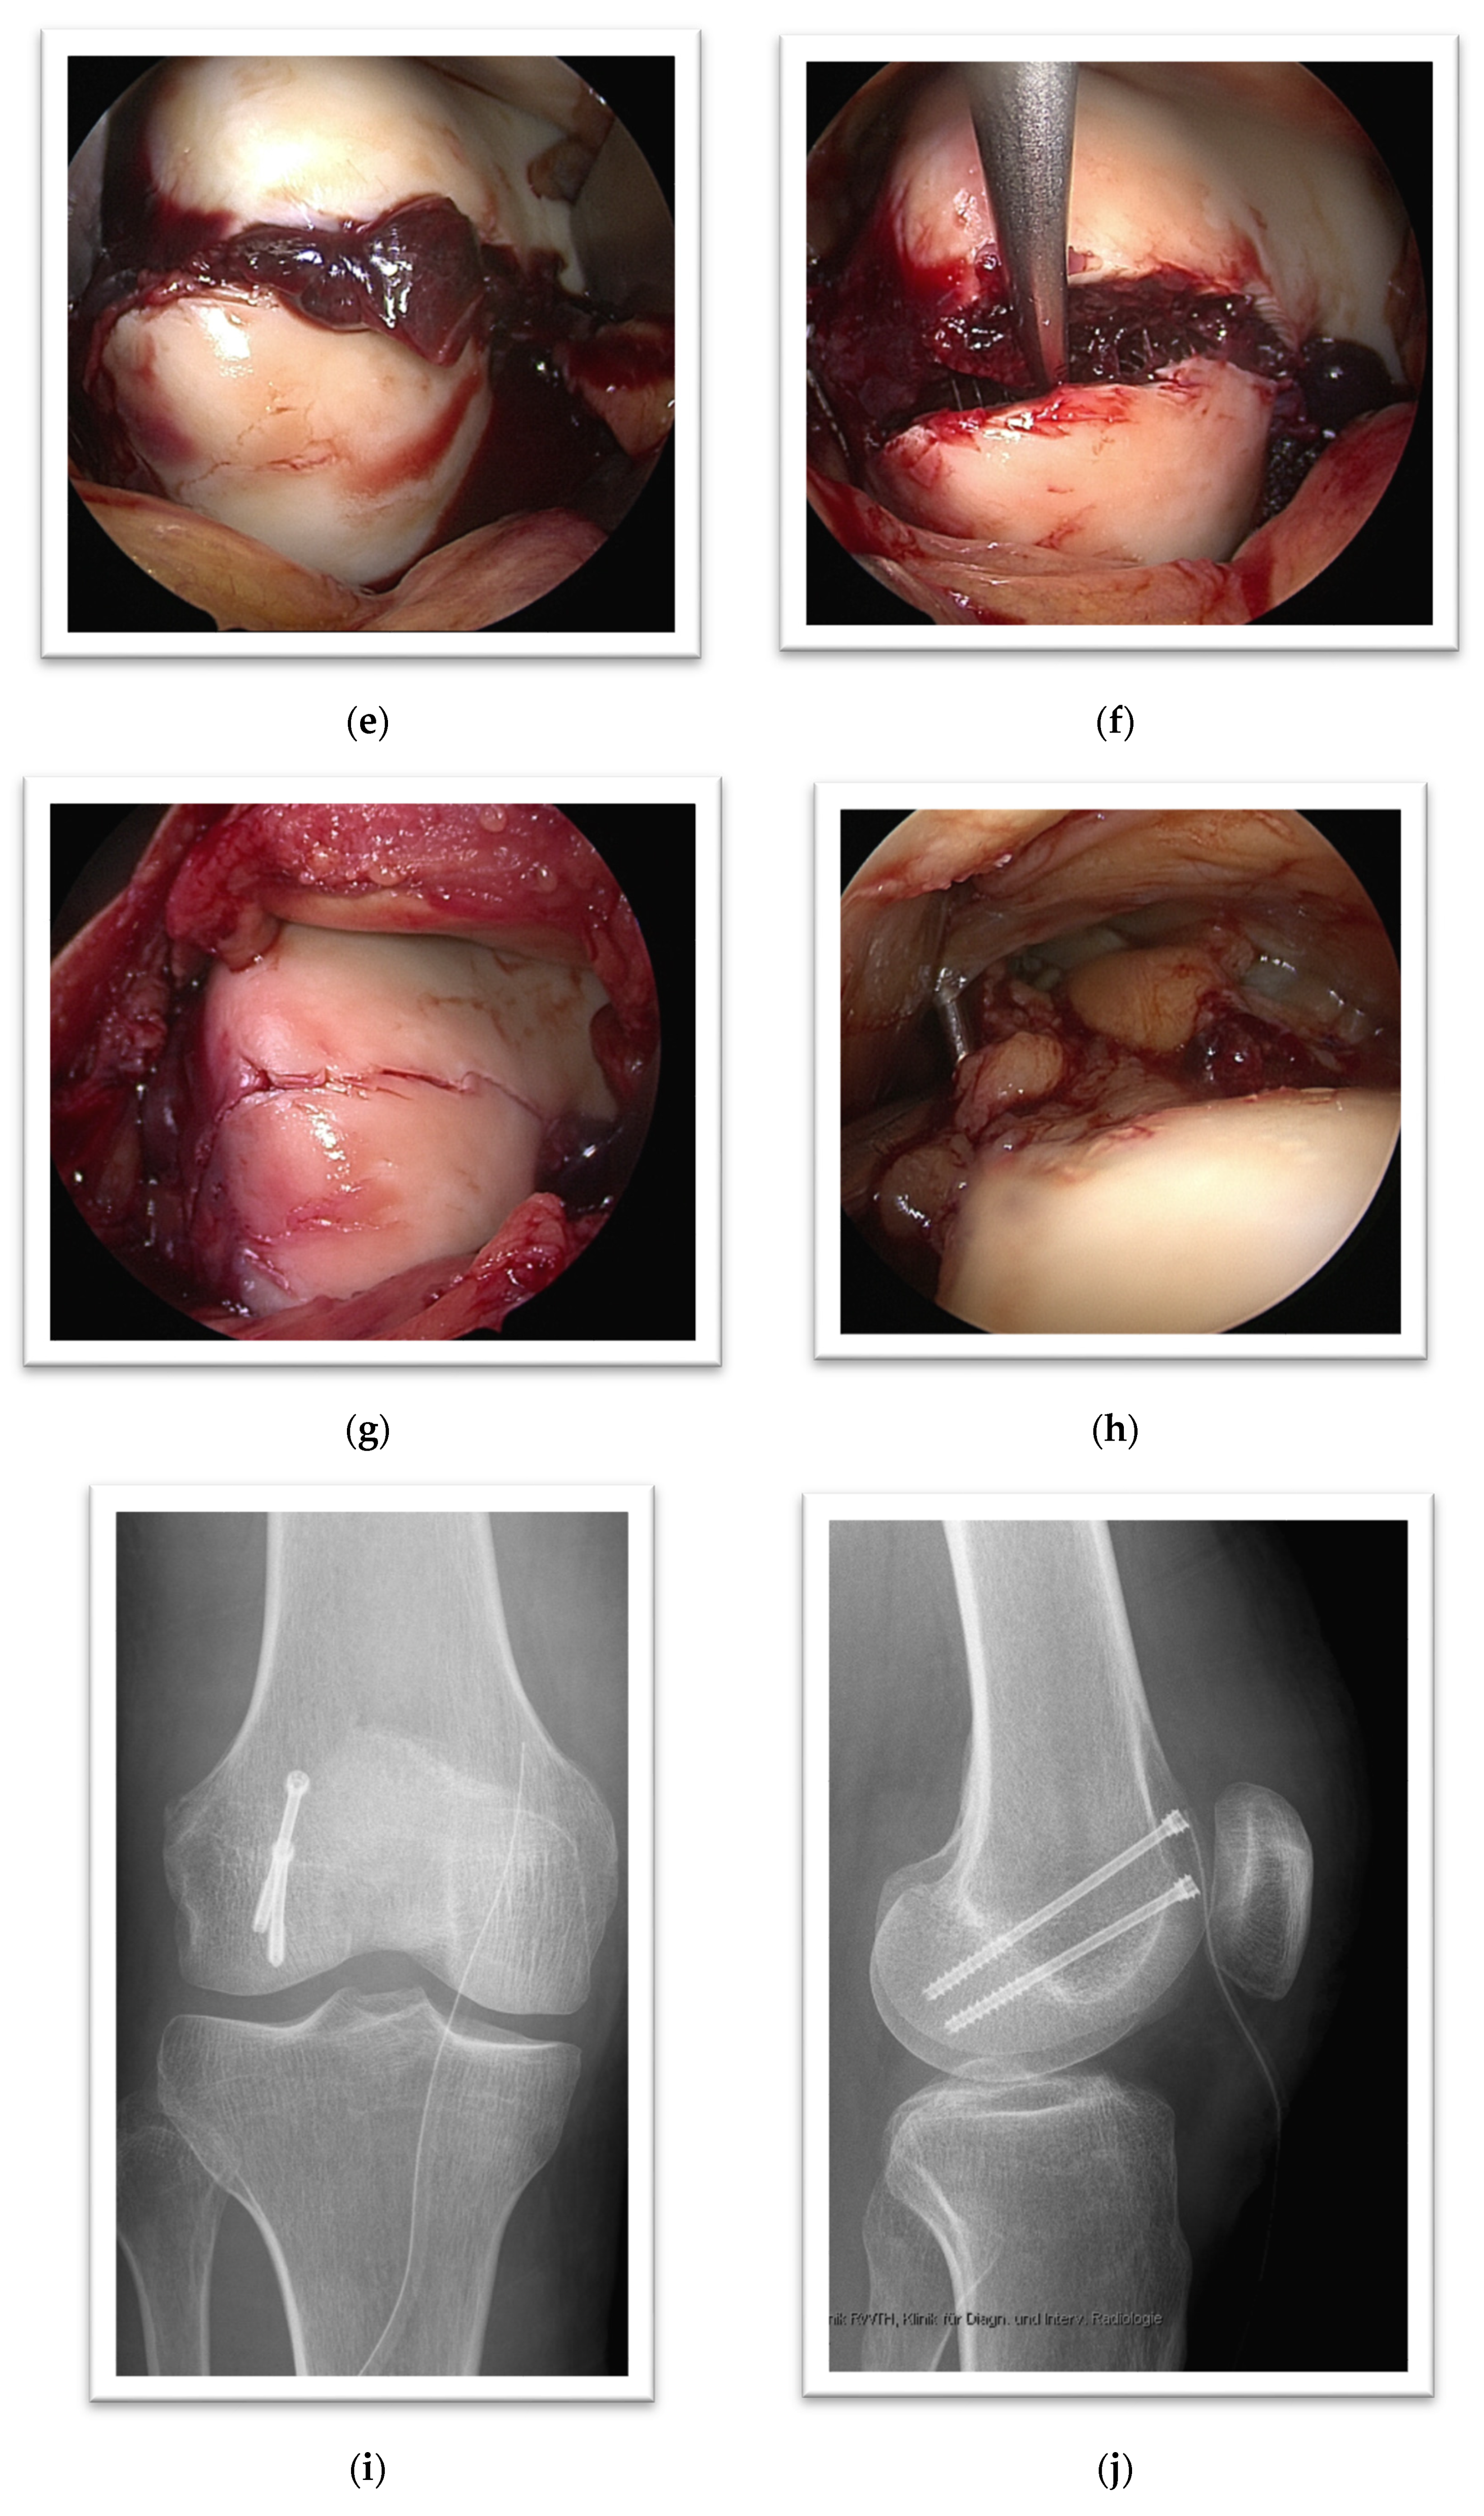

3. Case Presentation

4. Case Presentation

5. Case Presentation